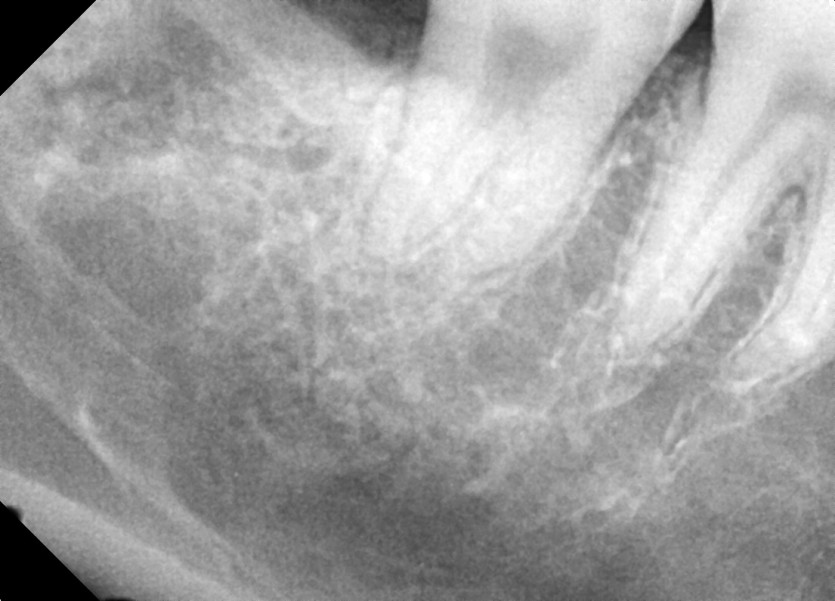

#18,48 사랑니 발치

구강외과 전문의가 당일발치 했습니다.